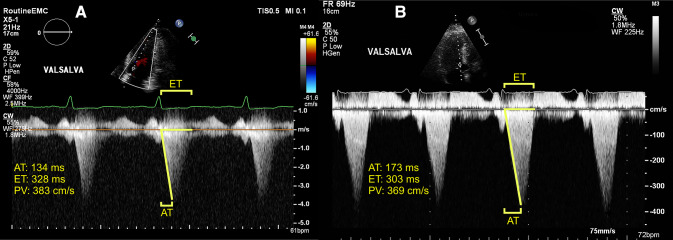

All patients underwent transthoracic echocardiography using a standardized acquisition protocol based on the recommendations of the American Society of Echocardiography and the European Association of Cardiovascular Imaging [12–14]. Continuous-wave (CW) Doppler tracings were recorded at rest and during the Valsalva maneuver. The left-ventricular (LV) systolic function was categorized as preserved (ejection fraction ≥ 50%) or reduced (ejection fraction < 50%) [15]. The LV diastolic function was defined as normal, abnormal relaxation, pseudonormal, or restrictive filling based on Doppler mitral inflow pattern parameters, including early (E) and late (A) LV filling velocities, E/A ratio, and tissue Doppler-derived septal early diastolic velocities (e′) [13]. An offline analysis of echocardiographic data was performed by an experienced sonographer (DB), unaware of the clinical characteristics. AT was defined as the time interval between the onset of flow over the LVOT and the moment of PV. LV ejection time (ET) was defined as the total time interval of systolic blood flow, corresponding to the opening and closing of the aortic valve. Acceleration was measured by dividing PV by AT. Measurements of AT, PV, and ET were performed by tracing CW Doppler signals over three consecutive beats or in five beats in images obtained during atrial fibrillation (Fig. 1). AT, PV, and ET were averaged to obtain a single value per patient. To assess reproducibility, the AT measurements were repeated in a random sample of 20 patients by a second investigator (RH).

Fig. 1.

Examples of continuous-wave Doppler tracings used for acceleration time measurement. a apical five chamber (zoomed) recording of 54-year-old asymptomatic man. b apical three chamber recording of 59-year-old man with complaints of exertional dyspnea and (near-)syncope (New York Heart Association class III). Peak left-ventricular outflow tract gradients during provocation were relatively similar, but acceleration time was distinctly different between subjects. Intervals for acceleration time and left-ventricular ejection time are represented as yellow brackets